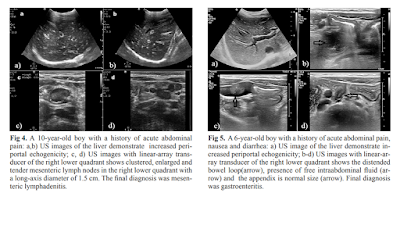

ErPC [echo rich periportal cuffing] appears especially in diseases

associated with abdominal inflammation such as gastroenteritis, acute

appendicitis, perforated appendicitis and mesenteric lymphadenitis. When

evaluated with adequate clinical information, the presence of ErPC is a

finding of high sensitivity and specificity in pediatric patients. This could

have a significant contribution to correct diagnoses by directing the

radiologists or clinicians to further examinations or follow-ups.